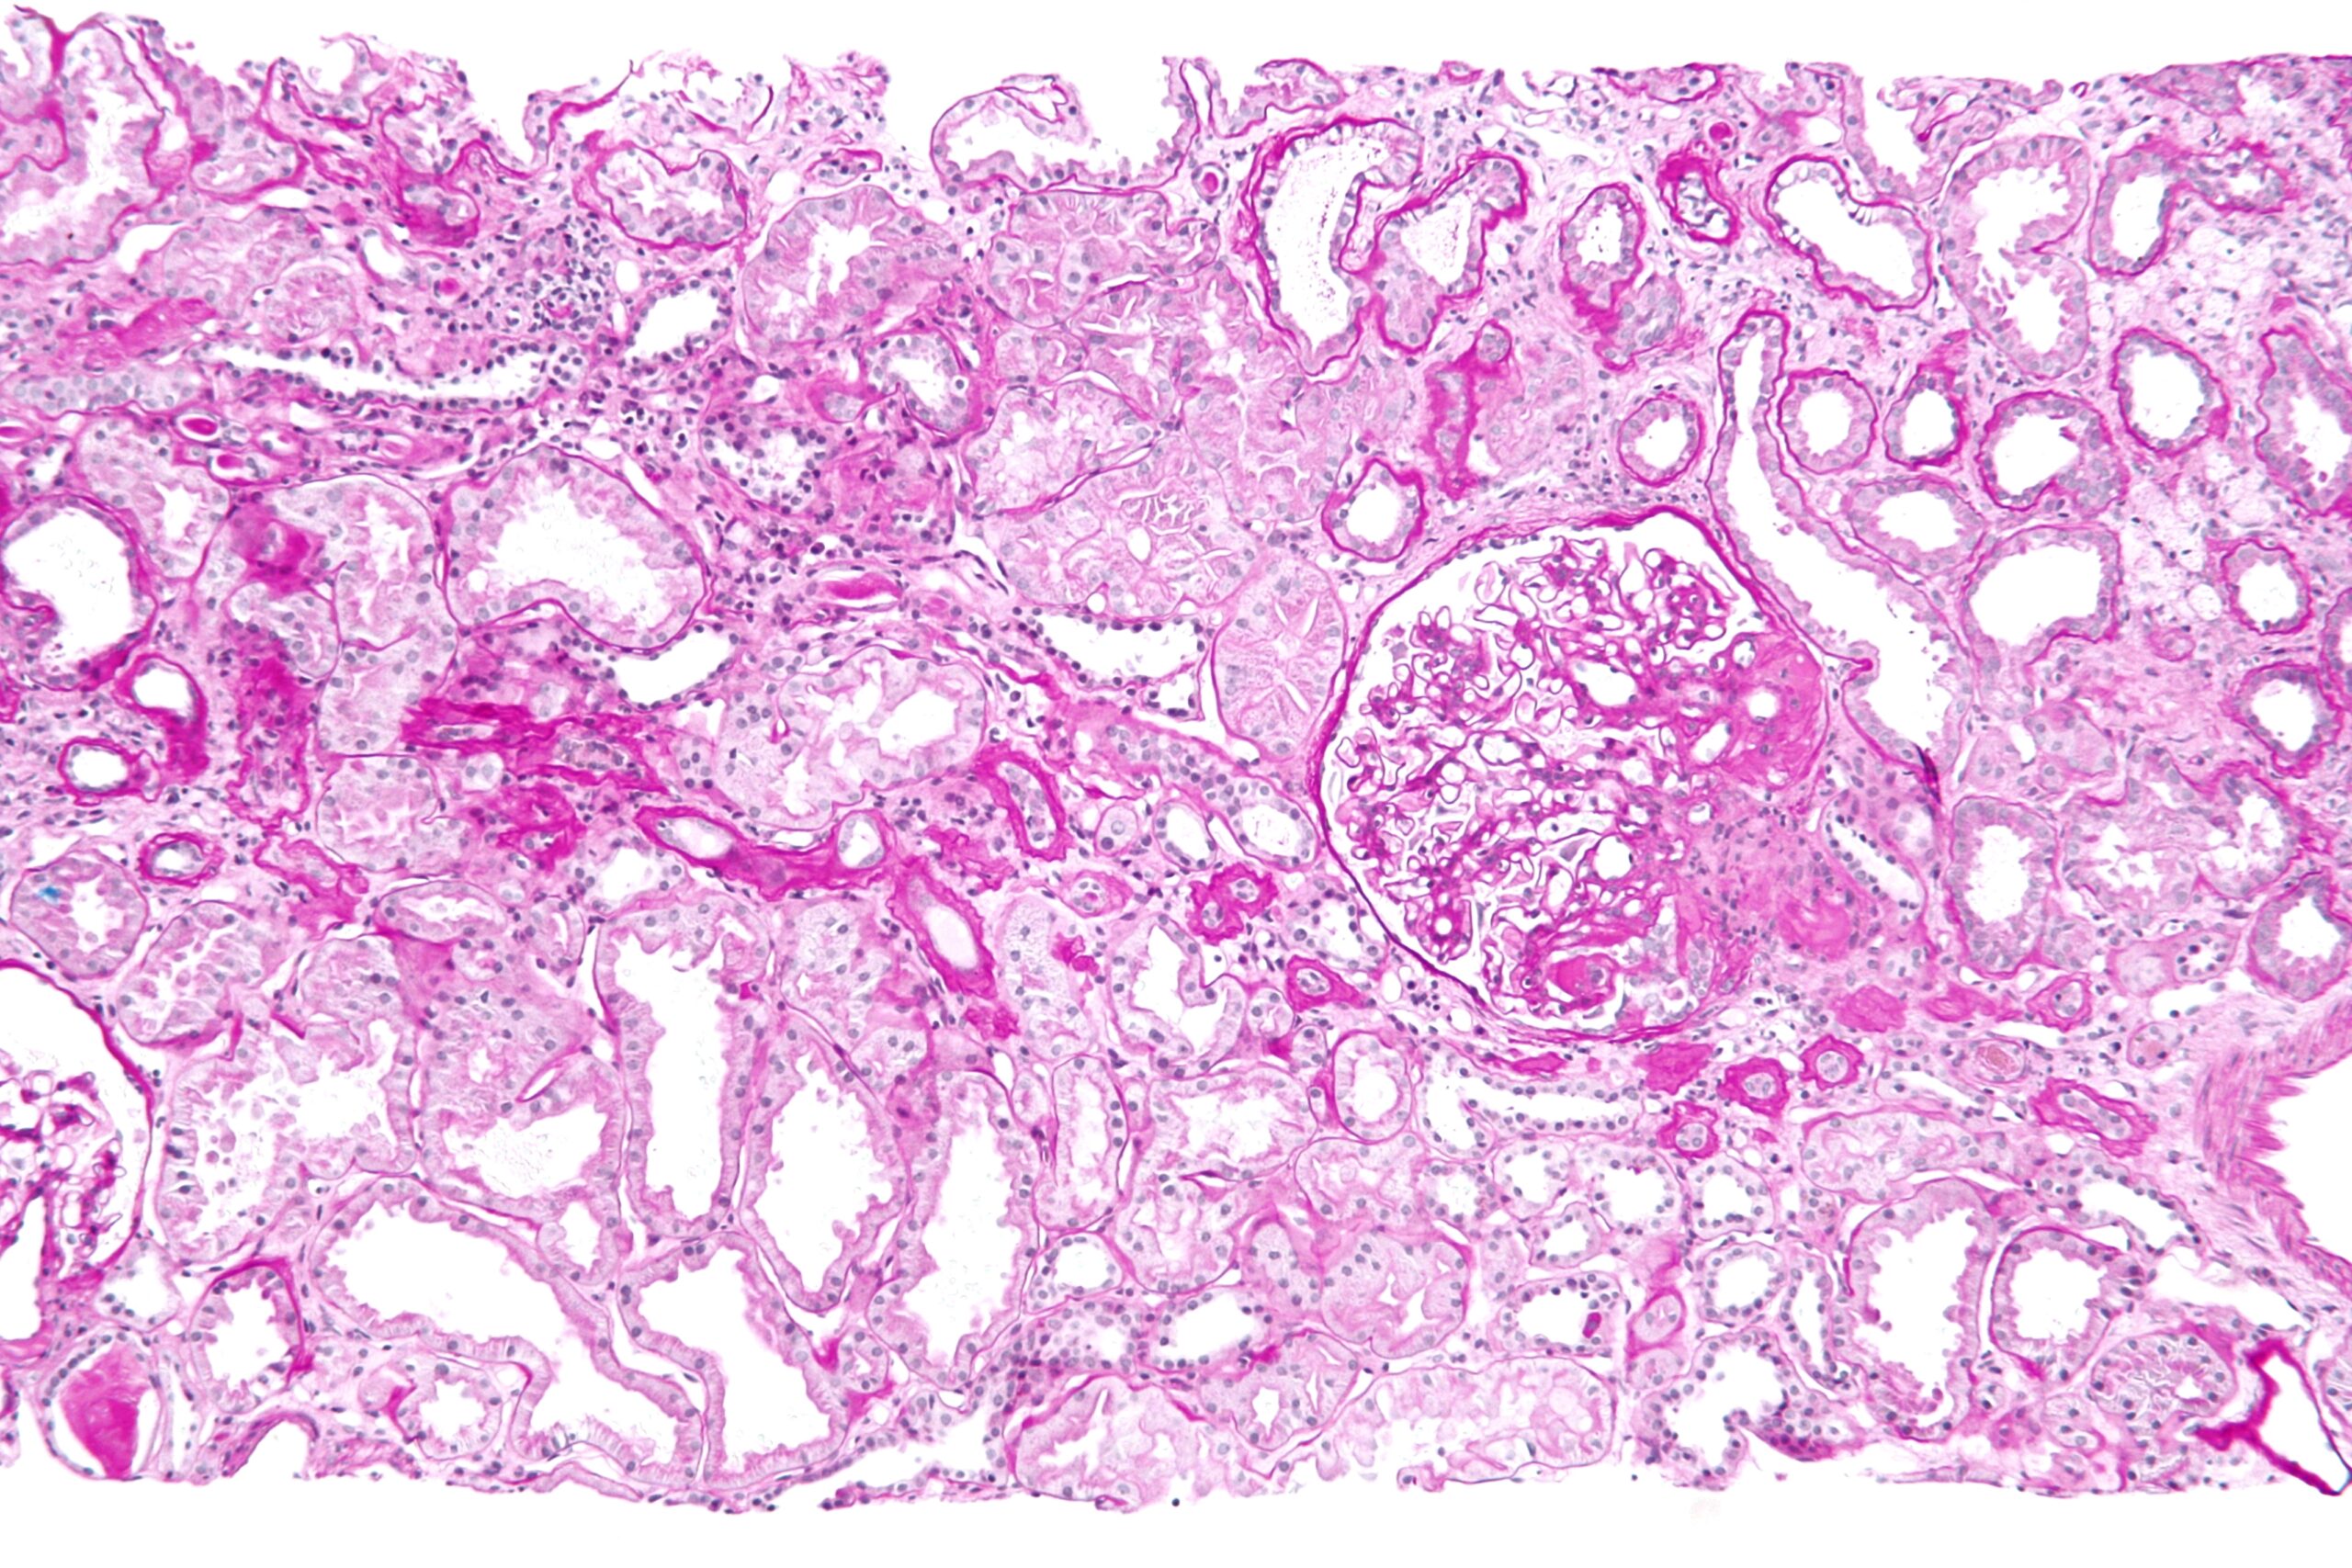

Once obtained, the biopsy sample is divided for multimodal analysis, yielding a definitive diagnosis in 95% of cases. Light microscopy (LM) examines paraffin-embedded sections stained with hematoxylin-eosin, periodic acid-Schiff (PAS), silver, and Masson’s trichrome, revealing glomerular, tubular, interstitial, and vascular changes. For example, it distinguishes proliferative from sclerosing glomerulopathies. Immunofluorescence (IF) on frozen sections detects immune deposits using antibodies against IgG, IgA, C3, etc., crucial for immune-mediated diseases like IgA nephropathy (Berger’s disease) or membranous nephropathy. Electron microscopy (EM) provides ultrastructural detail, identifying podocyte effacement in minimal change disease or subepithelial deposits in membranous glomerulopathy. Molecular techniques, like gene sequencing for hereditary nephropathies (e.g., Alport syndrome), are increasingly integrated.

Interpretation requires expertise from renal pathologists, correlating findings with clinical data. A typical report includes a semi-quantitative scoring system, such as the activity/chronicity index for lupus nephritis, influencing therapy. For instance, a biopsy showing crescentic glomerulonephritis might prompt urgent plasmapheresis and cyclophosphamide. In transplants, it detects antibody-mediated rejection via C4d staining. Limitations exist: sampling error (e.g., missing focal lesions) affects 5-10%, and artifacts from processing can mislead. Artificially intelligent tools are emerging to enhance accuracy.